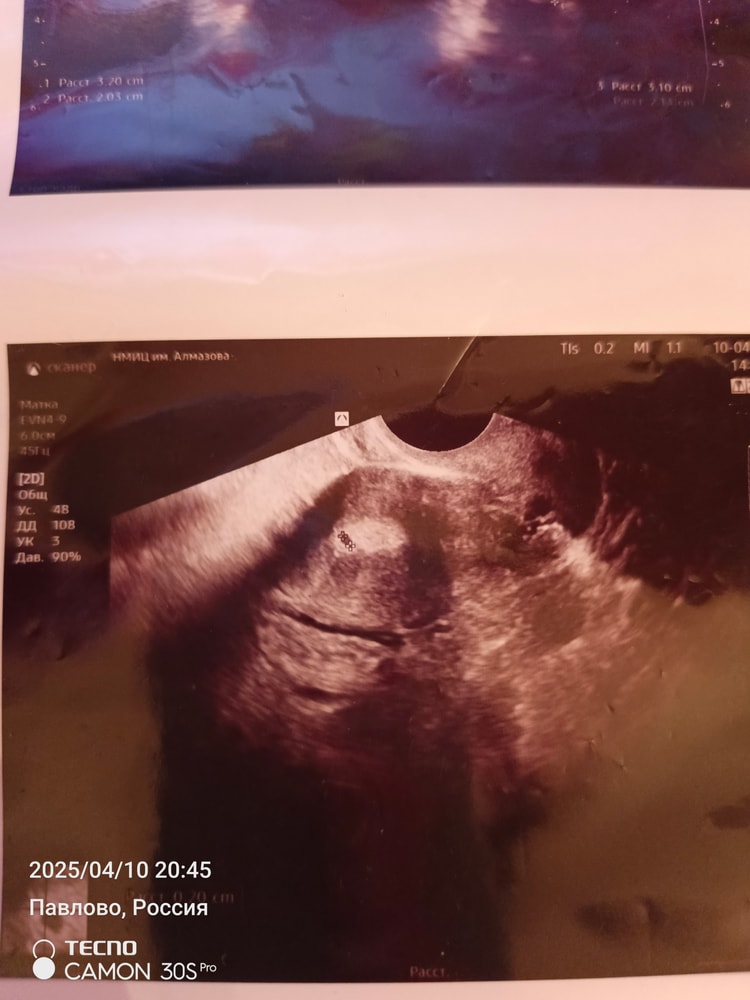

И так начнем чуть с далека, что имеем: 34 года, СПКЯ, 7 лет бесплодия, лишний вес. Муж на СВО мобилизовали в 22 году, соответственно отпуск раз в полгода. Естесно цикл гуляет, овуляция не стабильная. Я знаю что многие начнут писать что как так можно и все дела, но пост не для осуждения, а просто поныть и поддержать. И так сейчас плюс минус 40 день, если пьем дюфастон то цикл 30 дней. Муж уехал с отпуска 30.03. Дюф в том месяце не пила, да просто забила. Овуляция вроде была как я думала по ощущениям, но видать ошиблась. 01.04 делаю тест будьте уверены на дурака, получаю две полоски(естесно бегу на хгч-отрицательный) ну все думаю ладно не судьба мне забеременеть, обговариваю с мужем в отпуске что идем на квоту эко или что-то другое. Параллельно понимаю что надо скинуть 20 кг и в принципе к след отпуску буду готова, заодно сдам все анализы и схожу к репродуктологу. Иду по месту жительства к гинекологу мне выдают список мед центров в СПБ которые работают по омс эко. Выбираю Алмазова, записываюсь, сегодня была на приёме. Все как обычно анамнез собрала, анализы все сдала. Договариваемся с Ре что пью Дюфастон, смотрим овуляцию свою(стимулируемся) Муж приезжает в след отпуск и делаем инсеминацию, если нет идем на Эко. Идем делать с Ре узи, и тут она мне спрашивает когда был Муж, я говорю 30.03 уехал, и показывает мне точку 2 мм в матке. По УзИ вторая фаза, эндометрий серкреторный, но нет ЖТ. То есть ставит по узи беременность малого срока под вопросом, плодное яйцо 2 мм? Сказала ждать 7 дней и идти на ХГЧ, если не придут месячные. Смущает что нет ЖТ. Я конечно пошла взяла первый попавшийся тест в аптеке, думала ну может что-то будет. А там ничего такого и нет 🤷 Вообщем девочки вопрос в чём? Что ждать дальше? И как быть? Идти на хгч ? Я испытала шок, я вышла от нее в полном смятении, так как была уверена что не могу быть беременна. И она испытала небольшой шок от всей ситуации.